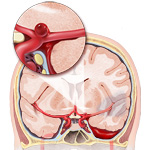

- Aneurysm ruptured

An aneurysm is a balloon-like bulge of an artery wall. As an aneurysm grows it puts pressure on nearby structures and may eventually rupture. A ruptured aneurysm releases blood into the spaces around the brain, called a subarachnoid hemorrhage, a life-threatening type of stroke. Treatment focuses on stopping the bleeding and repairing the aneurysm with clipping, coiling, or bypass.